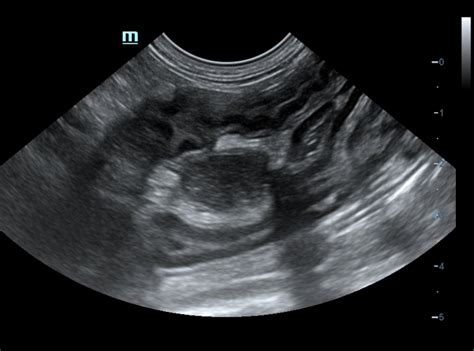

Pirmasis ultragarsinis tyrimas paprastai atliekamas 3 nėštumo savaitę, kuomet gemalinė pūslytė jau būna matoma gimdoje, stebimas širdelės plakimas. Vėliau, pagal Lietuvos Respublikos sveikatos apsaugos ministro įsakymą, būtini du ultragarsiniai tyrimai: vienas 11-14 nėštumo savaitę, kitas 18-20 nėštumo savaitę. Šių tyrimų metu vertinama placenta, vaisiaus dydis, būklė, judesiai, vaisiaus vandenų kiekis, smegenų ir virkštelės kraujotaka. Šiuo laikotarpiu, esant tinkamoms sąlygoms, gali būti nustatoma ir vaisiaus lytis.

Ultragarsinis tyrimas dažniausiai atliekamas per pilvo sienelę (transabdominaliniu būdu). Tam tikrais atvejais, ypač ankstyvose nėštumo stadijose, gali būti naudojamas ir makšties daviklis, kuris yra saugus ir padeda tiksliau įvertinti ankstyvą nėštumą, pavyzdžiui, nustatyti negimdinius nėštumus ar cistas.